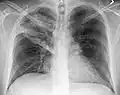

- Normal AP CXR

Normal lateral CXR